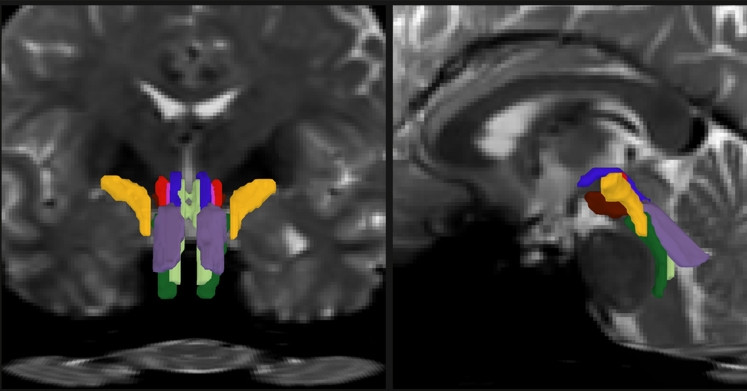

Thuật toán AI có thể ‘mở cửa sổ’ để quan sát những sợi trắng trong thân não

Một công cụ trí tuệ nhân tạo mới do các nhà khoa học tại MIT và Bệnh viện Đa khoa Massachusetts phát triển đang mở ra khả năng quan sát những bó sợi trắng trong thân não.